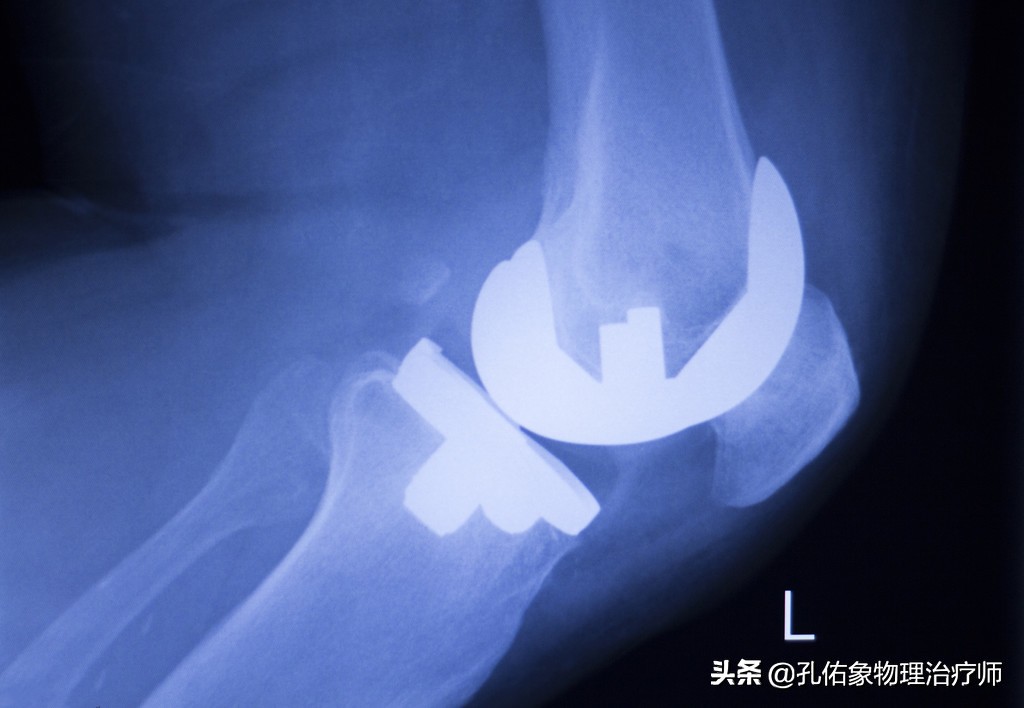

还有就是最后一种手术方法,做膝关节置换,就是把膝关节的结构截掉,换上假体膝关节,如下图:

膝置换术

置换术后,拍出来的X片是这样的。

置换后的X片

这个手术呢,相对还是比较成熟的;如果你真是处于这个阶段的问题,影响到你生活质量的话,直接选择这个手术吧,目前没有比这更好的解决方法。当然千万不可忽视术后的康复哈,手术后的康复决定你手术的成败,若是没有功能的膝关节,即使手术做得再完美,也是惘然。